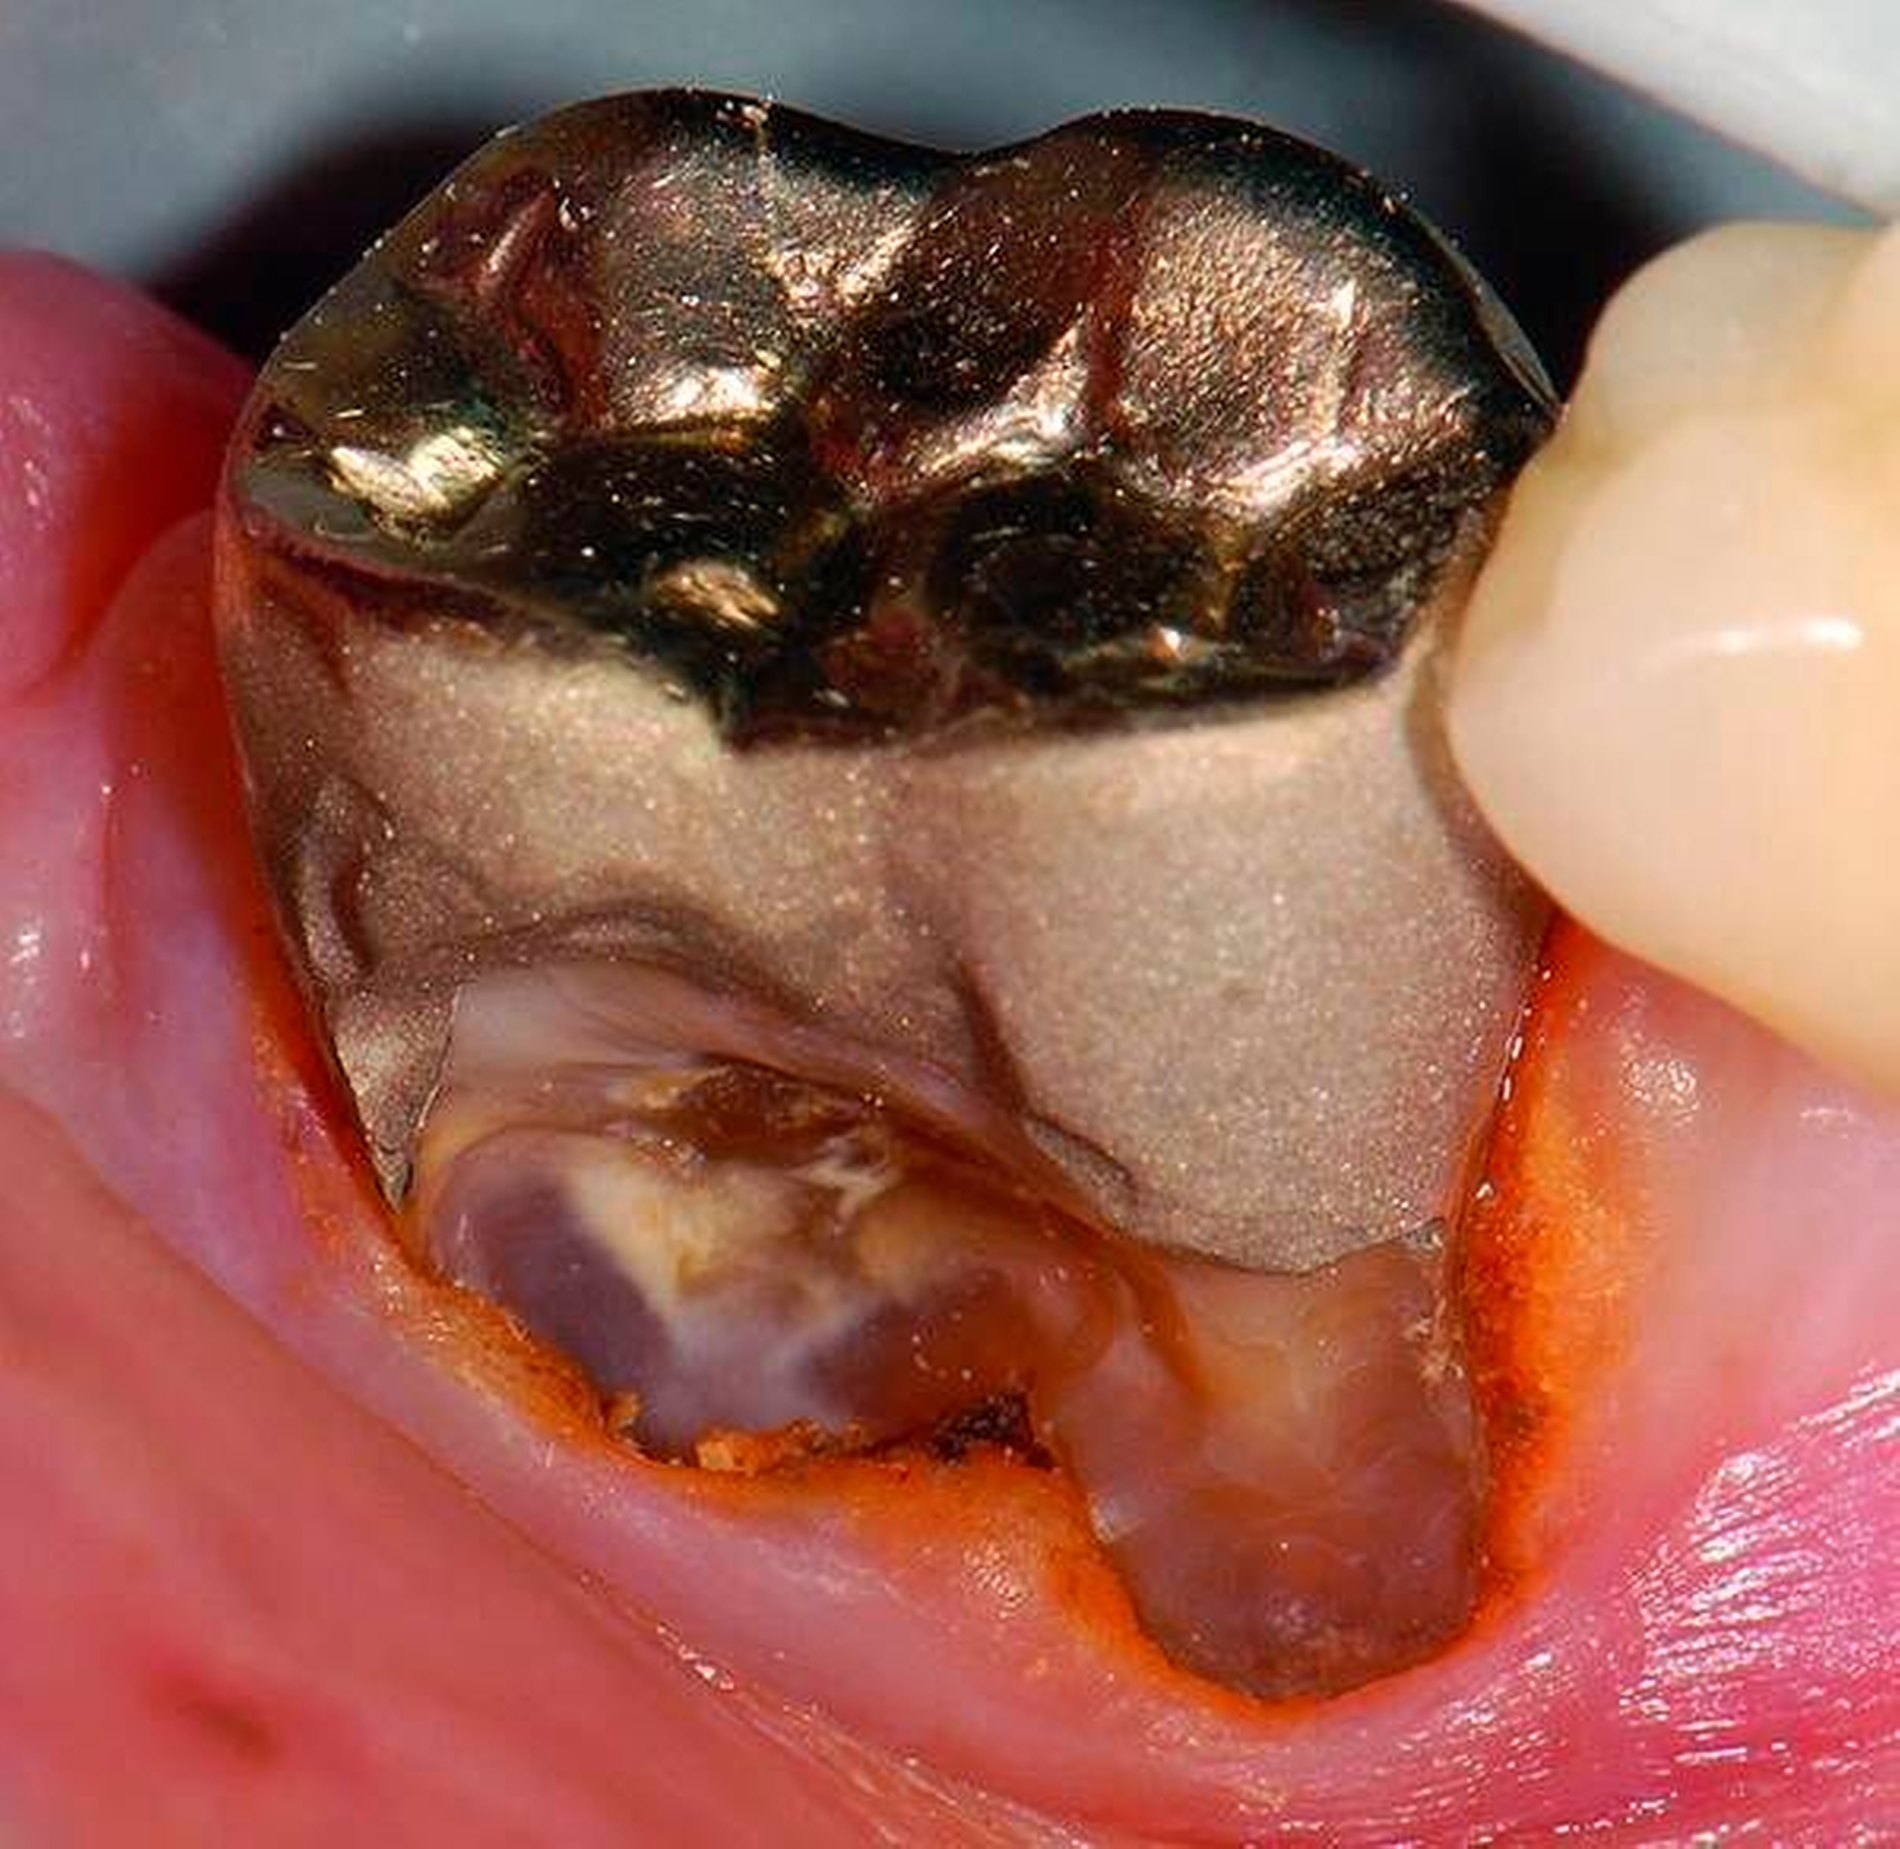

3. Restaurative Versorgungen bei Wurzelkaries

Freiliegende Wurzeloberflächen können im Alter ein locus minoris resistentiae für Karies sein. Im Zusammenspiel ungünstiger Ernährungsgewohnheiten, nachlassender Mundhygiene sowie Änderungen von Speichelquantität und -qualität kommt es zuweilen zu einem präventiv und restaurativ schwer beherrschbaren Auftreten von Wurzelkaries. Gut zugängliche Kariesläsionen können mit einphasig eingebrachtem Komposit (R1-Restaurationen) angegangen werden (Abbildungen 3 bis 5). Bei schwerer zugänglichen Arealen kommt ein zweiphasiges Vorgehen in Betracht (R2-Restaurationen). Das Vorgehen bei der R1- und bei der R2-Technik wurde mehrfach beschrieben [Frese et al., 2014a, b, c, d; Staehle et al., 2014, 2017]. Im Fall von zirkulärer Wurzelkaries sollte frühzeitig eingegriffen werden, da ansonsten die gesamte Zahnkrone frakturieren kann.

Abbildung 3: ausgedehnte Kronen- und Wurzelkaries unter einer Krone am Pfeilerzahn 47 einer seit Jahrzehnten eingegliederten Brücke von 45–47 bei einer 71-jährigen Patientin, die nach einer zerebrovaskulären Erkrankung unter Antikoagulantientherapie steht, vor etwa zwei Jahren hat sie eine Umstellung auf eine fluoridfreie Zahnpaste vorgenommen.